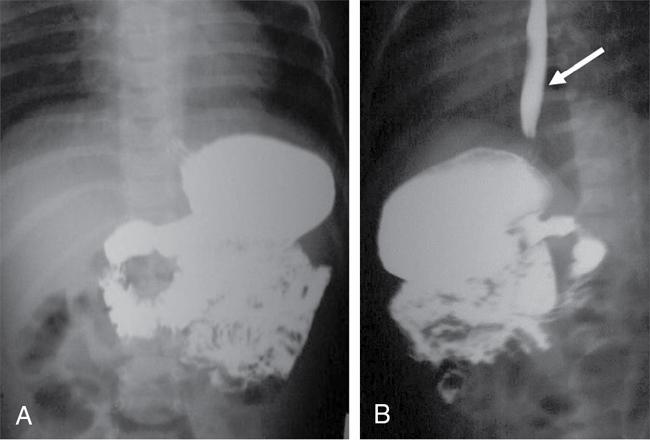

S. Muralinath, C.V. Kanimozhi, Krishnarjun M The focus and ambit of this chapter are restricted to the oesophagus as a subsequent author is dealing with the upper GI tract. Hence the narrative is confined to common problems like GER/GERD, achalasia, hiatus hernia, corrosive injury and ingested foreign bodies seen typically in infants and young children. The oesophagus is actually an anatomic and functioned continuum that serves essentially as a conduit between the hypopharynx and stomach. One cannot study the oesophagus in isolation without basic knowledge of the preceding structures and the following organs. Hence a brief consideration of the same is done along with the study of the oesophagus. The oesophagus basically transports the oropharyngeal contents onto the stomach. It goes without saying that there is bound to be an overlap or spillover of the proximal oropharyngeal and distal gastric disease onto the oesophagus. Dysphagia could be oropharyngeal or oesophageal and vomiting or regurgitation could be oesophageal or gastric. Hence the discussion will consider relevant proximal and distal elements in brief. Radiology and imaging play a significant role in the evaluation of children with upper GI tract diseases and is one of the most important sources of information for the clinician in the evaluation of GI tract diseases. The history and physical examination are crucial, but imaging plays a vital role in the assessment of GI tract disease. A plethora of investigative modalities are at one’s disposal today; hence, a good rapport between the clinician and the radiologist is essential in choosing the right investigations. Despite the advances in imaging technology and sophistry in techniques, the vast majority of the upper GI tract diseases in children, thankfully require only a few basic studies – conventional radiology (plain X-rays, fluoroscopy and contrast studies) and ultrasound. The downside is that in paediatric practice, these studies require in abundance practice and skill. Radiographic and fluoroscopic examinations are the mainstay in the study of upper GI tract disease in children. A preliminary plain film is the usual starting point; this supplemented by a few simple contrast studies and ultrasonography is all that is needed in the evaluation of most of the common upper GI tract diseases in children. It is mandatory that upper GI tract studies be done under fluoroscopic monitoring, as vital information is gained through the dynamics observed and the study is actively monitored and tailored to suit the clinical need. Barium is still the most commonly used contrast medium. Water-soluble contrast media are considered in specific circumstances as they are of value when the possibility of extravasation or perforation exists – for example, post-op evaluation of TEF repair. In the study of the oesophagus, hyperosmolar (ionic) contrast media are seldom utilized, as they may cause pulmonary oedema in the event of an aspiration. Nonionic low osmolar contrast media are preferred; especially in the newborn and young infant, because of the impact of ionic hyperosmolar contrast media on the water electrolyte equilibrium. To recognize the abnormal one has to realize the normal. The oesophagus is a relatively straight, hollow tube that follows the contour of the spine from the hypopharynx in the neck to the stomach in the abdomen. It has a relatively short cervical and abdominal segment with a long intervening thoracic component. It is governed at either end by high pressure zones. The upper oesophageal sphincter (UES) is defined by the cricopharyngeus, whereas the lower oesophageal sphincter (LES) is a poorly defined anatomic zone that is at and above the oesophago-gastric junction, partly straddling the diaphragmatic hiatus. The oesophagus has an inner mucosal layer lined mainly with stratified squamous epithelium which has negligible secretory and absorptive function. The outer muscular component has an external layer of longitudinal fibres and an internal layer of circular fibres. The musculature of the upper third is striated, whereas, in the lower third, it is nonstriated smooth muscle. The intervening segment is one of transition from the striated to the nonstriated. This nature of muscle distribution accounts for the central nervous system disorders affecting the motility of the pharynx and upper oesophagus, whereas autonomic system dysfunction leads to affliction of the lower oesophagus and the oesophago-gastric junction. The oesophagus at rest is in a collapsed state, bound at either ends by the UES and LES, respectively. These physiologic sphincter mechanisms maintain a tonic squeeze at rest generating a high pressure zone that prevents retrograde flow of contents from the oesophagus or the stomach. The function of the oesophagus is to propel contents from the pharynx onto the stomach. This is achieved through the mechanism of peristalsis. The pacemaker for the aboral, primary peristalsis is the act of deglutition. This once initiated travels down to the stomach. Peristalsis consists of a circular constrictive wave preceded by a wave of relaxation. This complex motor sequence is the result of the exquisite and intricate neural circuit (Auerbachian and Meissner plexuses) performing flawlessly in the gut wall. This wave drives the content in an aboral direction. While primary peristalsis is initiated by the act of swallowing, secondary peristalsis occurs in response to local oesophageal stimulus, the primary one being distention. This compliments the primary peristalsis in clearing the content. These propulsive mechanisms make sure that nothing stays in the oesophageal lumen, thus preventing stasis and its attendant complications. At rest, oesophagus is always kept in a collapsed state with no contents. Diagnostic tests commonly used in the evaluation of the oesophagus are oesophagogram, endoscopy and manometry. Endoscopy is for evaluating the oesophageal morphology, especially that of the lumen and the mucosa. Manometry offers information regarding the motor function; whereas an oesophagography provides information regarding both morphology and motor function and is usually the initial study in the evaluation of oesophagus. Barium is still the preferred contrast medium as it has the ability to provide a superior mucosal coating than any other contrast media. This coupled with its inherent density offers excellent contrast and detail. Barium is an inert substance with no adverse effect in the GI tract but that is not so when it leaks out and barium peritonitis is a much dreaded event. Water soluble low osmolar nonionic contrast media are considered when barium is contraindicated as in perforation. Water soluble hyperosmolar ionic contrast media are seldom used in paediatric practice as they cause airway and pulmonary compromise in the event of an aspiration. In newborn and young infants it can have a significant adverse effect on the water electrolyte equilibrium. The sole exception could be as therapeutic enema in meconium related disorders. Generally in paediatric practice a contrast swallow is seldom done in isolation. It is always a component of the upper GI series. The study is mostly done to evaluate vomiting or dysphagia. The problem could be in the oesophagus or elsewhere, for dysphagia could be pre-oesophageal and vomiting could be post-oesophageal. Contrast swallow may be done in isolation on follow-up studies, such as in post corrosive stricture, when the pathology has been localized, to evaluate the outcome of management. Be it a contrast swallow or an upper GI study, fluoroscopy is mandatory. Basic fluoroscopy and radiographic examination is the bedrock, when it comes to imaging evaluation of the oesophagus. An oesophagogram, as is the norm is done in conjunction with the upper GI series; wherein the mechanism of swallowing, the dynamics of peristaltic transit of content through oesophagus, stomach, duodenum and the proximal small bowel is studied along with it is morphology. Evaluation of the duodenum and DJ flexure is crucial for the documentation or exclusion of the rotational anomalies of the gut (Fig. 7.9.1). A standard operating protocol in a paediatric radiography suite would be: In children, especially the young ones, the oesophagus is a relatively simple structure and the mucosal folds are not that evident as in adults during a contrast swallow. But one can see often the extraneous impression caused by the aortic arch, the left main bronchus and the normal left atrium (Fig. 7.9.2). Normal peristalsis can be observed with the constricting ring preceded by the wave of relaxation leading to the aboral transmission of contrast. The peristalsis though, may not be as vigorous as in grownups. A word of caution during fluoroscopy – in the newborn and young infants the mediastinum and its structures are quite flexible and the oesophagus rather pliant. This will result in a peculiar configuration of the oesophagus during respiration. This is especially so if the infant cries leading to a bizarre and tortuous appearance of the oesophagus. To begin with this may be startling, but the entire process will settle once the crying induced Valsalva and the resultant elevation of intra-thoracic pressure eases. For the uninitiated a static film taken without fluoroscopy will be bewildering when viewed. Remember fluoroscopy is a must in paediatric upper GI study. A point to note is, small amounts of air in the oesophagus is not an uncommon finding in infants as they are quite aerophagic while feeding or even otherwise. Gastrooesophageal reflux (GER), hiatus hernia and achalasia cardia are considered in continuum as they essentially represent altered states at the same anatomic site – the oesophago-gastric junction. The literature on the anatomy and the physiology of the oesophagogastric junction is quite exhaustive; despite the various and numerous studies, the normal function of this junction defies clarity. GER as the name implies is the passage of gastric contents across the gastro-oesophageal junction into the oesophagus. The precise mechanism by which, aboral, unidirectional transit of content occurs at the oesophago-gastric junction is still not clearly understood. Various factors and mechanism are said to play a part in the valve like function of the oesophago-gastric junction. Apparently, the most important factor is the high pressure zone in the lower oesophagus representing the LES. A segmental tonic mechanism is considered to be operative in maintaining the high pressure. The other contributory factors said to assist mechanically are, the pinch-cock effect of the decussating crural fibres of the diaphragm, the unique anatomy of the junction providing the angle of His, the mucosal flap-valve mechanism, the posterolateral location of the fundus and the length of the intra-abdominal oesophagus. Transient relaxation of the LES is considered to be the primary mechanism by which reflux is said to occur. An autonomic, vagus mediated reflex regulates the transient relaxation of the LES. This relaxation reflex can be initiated by gastric-distention or by the initiation of swallow even when not leading to oesophageal peristalsis. The diagnosis of GER is made on a clinical basis from the history and physical examination. GER in a healthy, thriving infant is a physiologic and self-limiting entity. It is mostly managed by empirical and conservative measures along with parental reassurance. It is essential to differentiate physiologic GER from the pathologic state – GER disease (GERD). In GERD, as the name implies, the infant or child is no longer at ease. When GER is frequent and persistent leading to troublesome symptoms or complications, then what you have at hand is GERD. GER can have GI symptoms as well as non-GI related symptoms, like the oft stated peculiar manifestation of neck contortions in Sandifer’s syndrome. Reflux of acid content on to the airway may cause apnoea, cyanotic spells and the much dreaded sudden infant death syndrome. Another subset is there with silent or occult GER. In these infants or children, the GER does not manifest as regurgitation, vomiting or rumination. It is because these reflux does not quite reach the oral cavity to manifest as symptoms and yet could potentially be as harmful. Hence investigation is done to evaluate occult GERD and in high risk groups (neurological disorders, trisomy 21 and chronic respiratory ailments as in cystic fibrosis) suspected to have silent GER. An ideal oesophageal test should detect GER, establish a causal relationship between the event and disease, provide information about the nature and extent of reflux, detect the pathologic changes wrought by the disease and establish a differential diagnosis if any. This is a tall order and as expected no single test can provide all the information. Hence the tests need to be done in a judicious manner depending on the information required. This study has been the traditional choice; but it has several limitations. It lacks sensitivity and specificity. GER is a 24 hours diurnal event and any study that focuses on a brief period of time is certainly at a loss. As yet there is no universally standardized technique. Ideally the study should be done on a relatively relaxed and comfortably restrained supine infant. The infant is fed barium through a feeder with the head end slightly elevated. Adequate barium, comparable to a normal feed volume is ingested to fill the stomach. The infant should be supine now. During this period, judicious, intermittent fluoroscopy is utilized to observe the dynamics of swallowing, oesophageal transit and once the stomach is adequately full, for the occurrence of reflux (Fig. 7.9.3). Provocative measures to elicit reflux is best avoided as they do not represent a physiologic event. Clear fluid or water may be given to washout the oesophagus when needed, and to look for GER; as this can be considered to simulate a life event. Once that is done, passage of barium from the stomach to the proximal small bowel is observed. This is done to evaluate the duodenal ‘C’ loop and the DJ flexure to exclude malrotation and other obstructive pathologies. The study has to be as brief as possible as one is dealing with ionizing radiation. The upper GI series is not for just documenting GER but done to evaluate other causes of vomiting as it provides excellent anatomic information along with motor function.